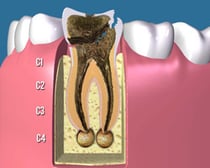

C4:

虫歯によって、歯の頭の部分がほとんど崩壊してしまった状態です。残っている歯根の状態によっては抜歯になることも多くあります。歯を残す場合も、難易度の高い根管治療が必要で、歯根に深く維持を求める「差し歯」になります。治療後も「差し歯」によって歯根が割れるリスクが残ります。

根尖病巣:

歯の神経に細菌が浸入して、歯根を伝って歯根の先で感染した状態です。歯の神経が無くても咬んだときに痛みがでます。

重篤な場合は、歯ぐきや顔まで腫れてきたり、ズキズキ痛くなったり、膿が出てきたりします。

通常、根管治療によって治していきますが、重篤なケースではマイクロスコープ治療や外科的根管治療が適応になったり、抜歯に至る場合もあります。